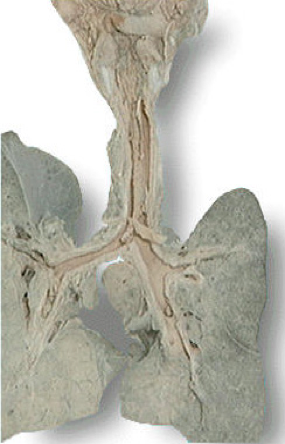

当纤维素性炎发生于浆膜和肺时,少量纤维素渗出,可溶解吸收;多量纤维素渗出则容易发生机化,甚至浆膜腔闭塞,引起器官功能障碍。

如纤维素性心包炎,由于心脏的博动,心包的脏壁两层相互摩擦,使渗出在心包腔内的纤维素在心包膜表面呈绒毛状,称为“绒毛心”。 |

结局:若中性粒细胞渗出较少,释出的蛋白水解酶相对不足,不能将纤维素完全溶解吸收时,可通过肉芽组织的长入而发生机化,最后导致纤维化。发生于胸膜者造成胸膜增厚与粘连,甚至使胸膜腔闭塞。发生于肺者,如大叶性肺炎的灰色肝样变期,肺泡腔内有大量纤维素渗出,使肺实变。

右肺和胸壁之间的粘连 |